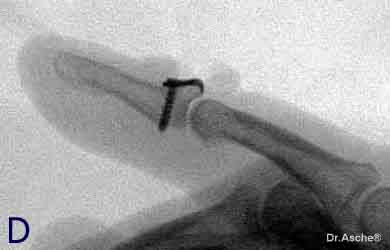

Die Microplatte (Fa. Leibinger) wird nun so plaziert, dass der Kirschnerdraht exzentrisch zwischen den Kaken zu liegen kommt. Danach wird die Platte mit einer Schraube fixiert. | ||

Exakte Positionierung der Hakenplatte. Das Fragment

ist nun stufenfrei fixiert. Übungsstabilität ist nach

der Wundheilung gegeben.